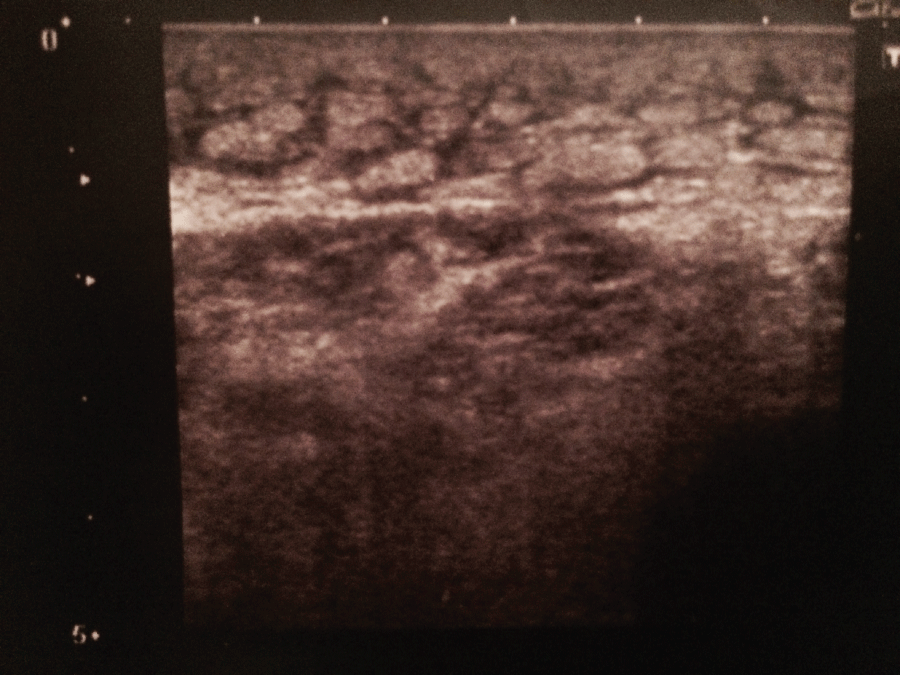

After 20 sessions of treatment, all patients of both groups obtained an improvement of knee extension: in group A, mean knee extension improved from T0 (+ 25° ± 5°) to T1 (+ 5° ± 2°) (p < 0.0001); similarly in group B an improvement of mean knee extension from T0 (+ 27° ± 4°) to T1 (+ 13° ± 4°) (p = 0.0001) was observed (Table 2). However, comparing data at T1 in two groups, there is an improvement statistically significative in patients treated with coadiuvant treatment of SMV rather than patients treated only by general physical therapy (from + 5° ± 2° of group A, to + 13° ± 4° of group B, p < 0.0001). Table 3 to ultrasound evaluation, in two patients of group A, a marked thickening and soaking of subcutaneous adipose tissue, with signs of hyperechoic lobular organization, were observed, particularly in correspondence of the third distal of quadriceps muscle (about 8 cm from the patella*, a maximum of 2.4 cm thickening of subcutaneous adipose tissue was observed) figure 1 and on the residual limb; in other patients of group A and B, a normal thickness and echogenicity of muscle and subcutaneous tissues were observed. After 20 sessions of SMV treatment, in these two patients of group A, a reduction in thickness/soaking and lobular organization in subcutaneous adipose tissue were obtained (a maximum of 1.3 cm thickening was observed in the same side*) figure 2; in remaining patients of both groups no tissues modification were observed after treatment with physical therapy and SMV. To X-rays, in all patients of both groups A and B, typical signs of osteoarthritis were observed.

Figure 1: Marked thickening and soaking of subcutaneous adipose tissue in correspondence of the third distal of quadriceps muscle (about 8 cm from the patella, a maximum of 2.4 cm thickening, with signs of hyperechoic lobular organization, were observed). View Figure 1

Figure 2: Reduction in thickness/soaking and lobular organization in subcutaneous adipose tissue (about 8 cm from the patella, a maximum of 1.3 cm thickening was observed), after 20 sessions of SMV treatment. View Figure 2